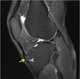

Bone marrow edema syndrome